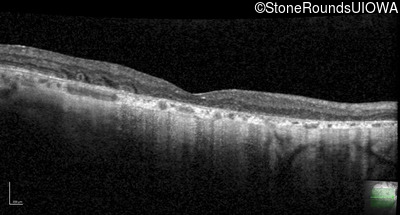

Optical Coherence Tomography - Right - 20/100 +1

Exemplar / OCT Stack